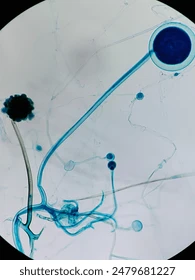

Aspergillus spp